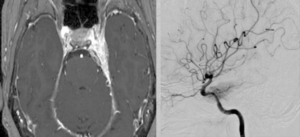

手術は通常通り行われ、顔面神経の麻痺を起こさずに摘出は終了し、うまくいったと考えていました。しかし術後より覚醒障害が続き、強い小脳腫脹を生じたため、術後脳室ドレナージ術、バルビタール麻酔療法、気管切開まで行い急性期を乗り切りました。術前より下肢静脈血栓症を合併していたことと、Petrosal veinが通常より広範囲の静脈環流を行っていたためと考えられます。現在、覚醒し、四肢が動くようになってきました。

手術は通常通り行われ、顔面神経の麻痺を起こさずに摘出は終了し、うまくいったと考えていました。しかし術後より覚醒障害が続き、強い小脳腫脹を生じたため、術後脳室ドレナージ術、バルビタール麻酔療法、気管切開まで行い急性期を乗り切りました。術前より下肢静脈血栓症を合併していたことと、Petrosal veinが通常より広範囲の静脈環流を行っていたためと考えられます。現在、覚醒し、四肢が動くようになってきました。